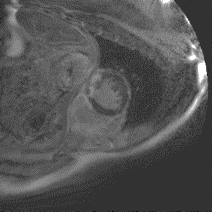

Although supervised deep-learning has achieved promising performance in medical image segmentation, many methods cannot generalize well on unseen data, limiting their real-world applicability. To address this problem, we propose a deep learning-based Bayesian framework, which jointly models image and label statistics, utilizing the domain-irrelevant contour of a medical image for segmentation. Specifically, we first decompose an image into components of contour and basis. Then, we model the expected label as a variable only related to the contour. Finally, we develop a variational Bayesian framework to infer the posterior distributions of these variables, including the contour, the basis, and the label. The framework is implemented with neural networks, thus is referred to as deep Bayesian segmentation. Results on the task of cross-sequence cardiac MRI segmentation show that our method set a new state of the art for model generalizability. Particularly, the BayeSeg model trained with LGE MRI generalized well on T2 images and outperformed other models with great margins, i.e., over 0.47 in terms of average Dice. Our code is available at https://zmiclab.github.io/projects.html.